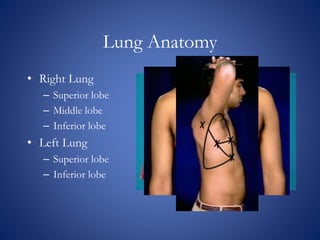

The document discusses chest x-rays and how to analyze them. It describes how densities appear on x-rays, with gas being darkest and bone being lightest. Proper inspiration, penetration, and rotation are needed for quality images. The lungs, heart, bones, and other structures are then analyzed systematically. Common findings like consolidation and air bronchograms are also explained.